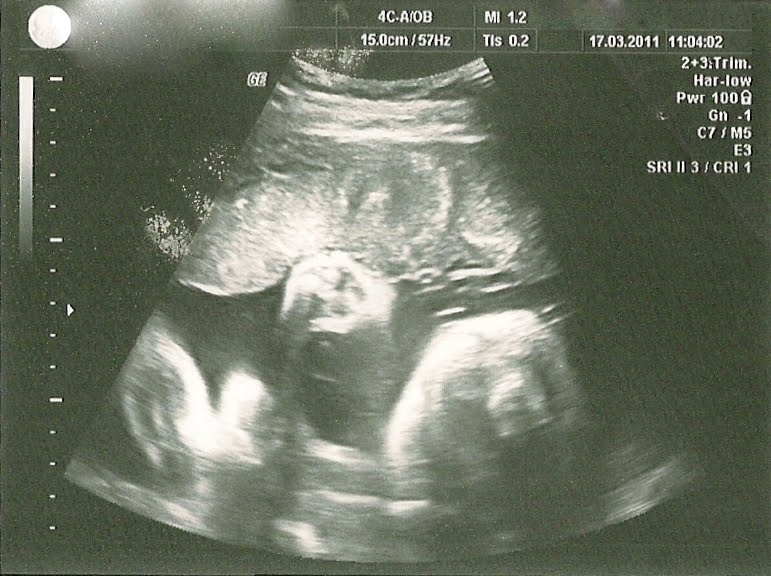

On 17.3.11 W 31(6), we could see poupik with a cephalic head presentation, following some time he preferred to have the head up. Estimated to weight about 2 kg.